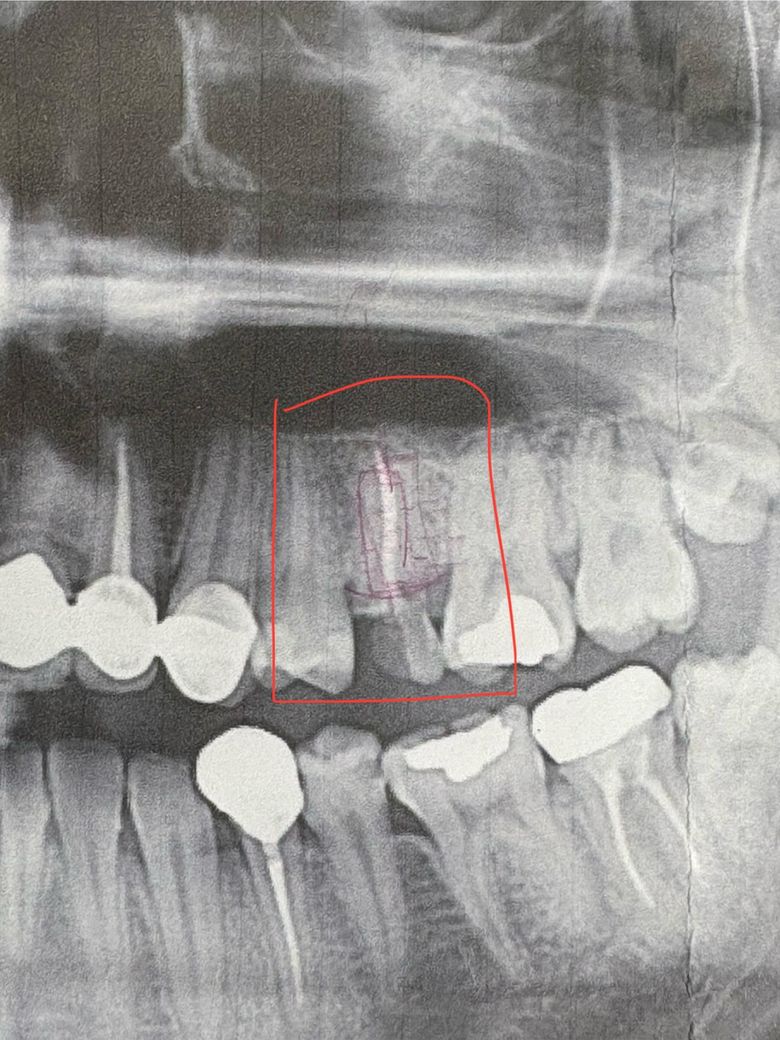

금일 가까운 동네 치과에서 사진 촬영과 함께 상담을 받아본 결과, 촬영된 사진은 아래 사진 처럼 나왔구요 동네 치과에서는 무조건 발치한 이후 임플란트를 진행 해야한다고 답변을 받았습니다.

• 2번 째 사진

사진을 봤을 경우 충치나 파절된 부위가 치조골 부위에 근접한 것으로 보입니다.